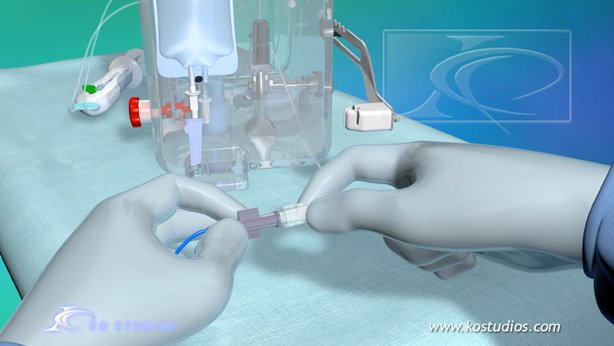

EnCompass F2 Device for cerebral embolic protection system in TAVR procedures

EnCompass Technologies

EnCompass’ F2 filter has pores small enough to block most emboli to the brain while preserving blood flow. During the TAVR procedure, 360-degree wall apposition of the filter in the aortic arch prevents migration. The filter, attached to a self-expanding, nitinol stent, is easy to insert, deploy and retrieve, according to the company. Copyright ©2021 KO Studios.